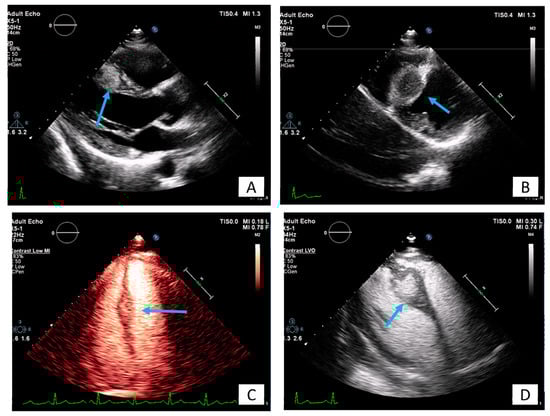

3.2. Transesophageal Echocardiography